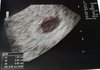

Jak to?? Nie. Ja do konca wierze!!!U mnie lipa dziewczyny. 27dpt blastek i nie ma echa zarodka. Pecherzyk 10,07.

W 17dpt był 7,3 z widocznym YC...

Koniczynko, to nie pomylka na usg? Trzymam kciuki z calej sily, aby jednak wszystko bylo ok. Czytalam z usmiechem, ze wkoncu wszystko ok u was, tyle dobrych wiesci. Trudno mi zrozumiec, czemu teraz taki obraz usg![]()